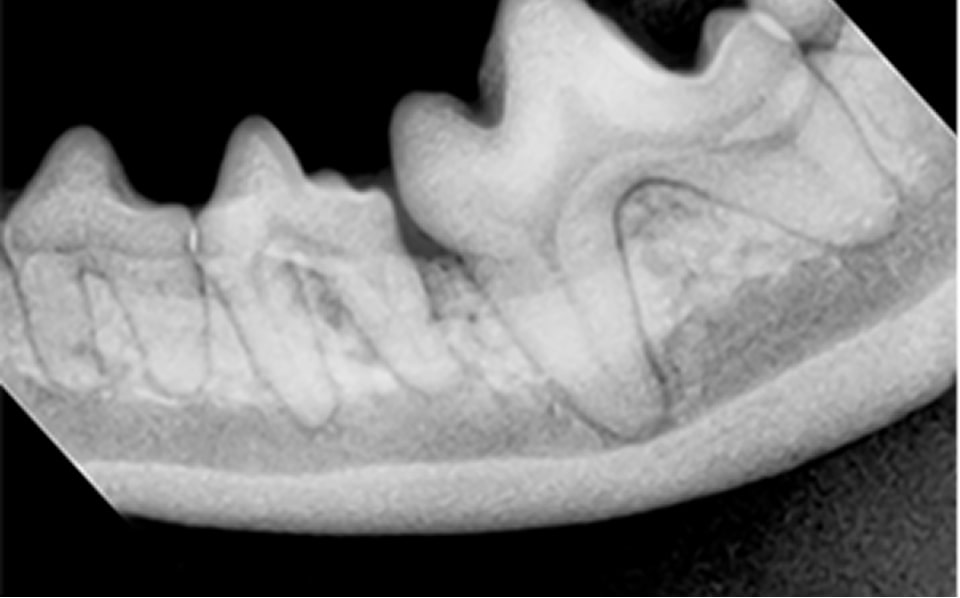

軽度歯周病

処置前

処置後